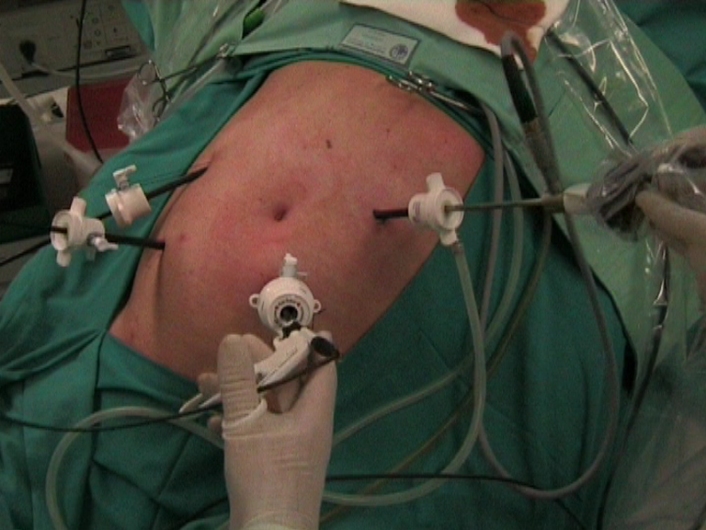

La colectomía laparoscópica consiste en practicar la extracción de una parte del colon, sin abrir el abdomen, trabajando a través de cuatro pequeños orificios (de 5 y 12 mm) por donde se introducen una cámara y el instrumental de disección, corte y sutura necesarios.

El fragmento de intestino grueso se extrae por una pequeña incisión de 5 cm situada la mayoría de las veces en la zona más inferior del abdomen.